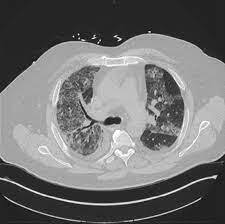

Tosse, febre e dispneia arrastados com esta imagem. Qual o diagnóstico?

Obs: 2 Testes para Covid negativos.

A

Proteinose Alveolar Pulmonar

Tratamento: Lavagem pulmonar total.

Os corticoides sistêmicos não têm qualquer papel no tratamento.